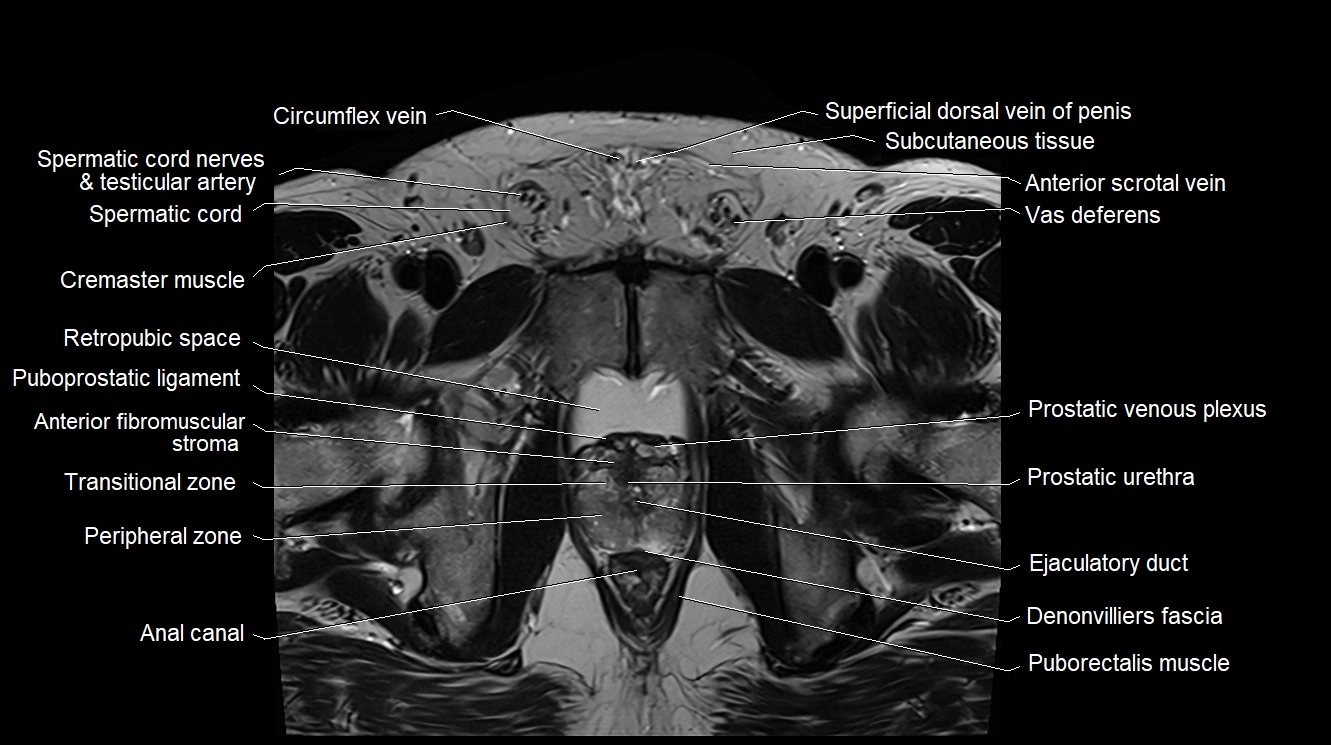

- Anterior Fibromuscular Stroma of prostate

- Cremaster muscle

- Ejaculatory duct

- Peripheral zone of prostate

- Prostatic urethra

- Puboprostatic ligament

- Puborectalis muscle

- Rectoprostatic fascia (Denonvilliers' fascia)

- Retropubic space

- Spermatic cord

- Spermatic cord nerves

- Superficial dorsal vein of penis

- Transitional zone of prostate

- Vas deferens